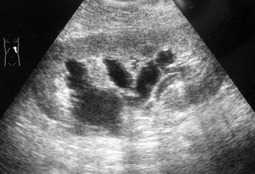

Женщина 54года. Профосмотр, случайная находка

- IMG_6686=.jpg (25.73 КБ) 5734 просмотра

Синусные.

Если не уверены - сделайте внутривенную экскреторную урографию.